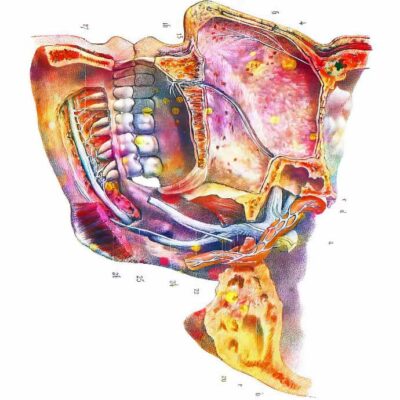

Tableaux murale pour la décoration intérieure d’un cabinet médical dentiste